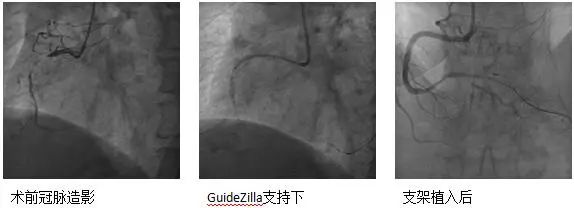

CTO病变:患者74岁男性,主因胸痛10余天,憋气1周余,加重2天入院,既往高血压、糖尿病病史、长期吸烟史。诊断急性非ST段抬高型心肌梗死、心力衰竭。强化用药改善心功能后择期行冠脉造影示LAD为CTO,RCA近段CTO病变、全程钙化影,圆锥支向LAD远端提供侧支循环。患者拒绝CABG治疗,决定开通RCA CTO。但患者RCA严重钙化,GW在微导管支持下通过CTO段,但应用普通球囊预扩后,无法送入IVUS导管,遂果断选择GuideZilla支持下Shockwave冲击波球囊治疗,成功植入支架,手术效果良好,为进一步解决LAD病变奠定了基础。